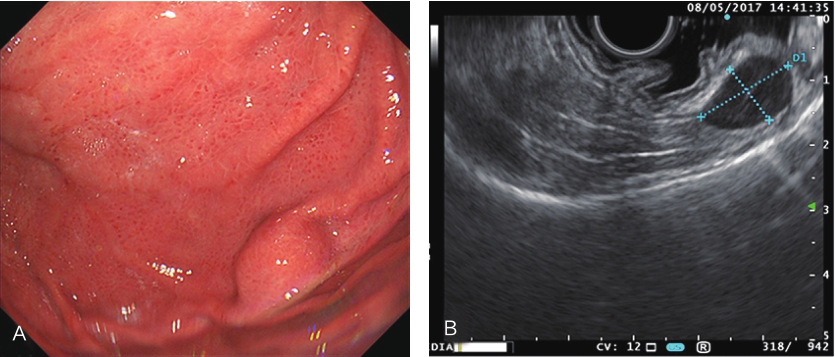

超声胃镜示:胃腔空虚,胃底可见隆起,约1.5cm,黏膜完整,上距贲门齿状线约4~5cm。超声:7.5~12MHz探查病变处第1~3层连续完整,第4层内可见一圆形低回声,界限清楚,约15.6cm×9.9mm大小,中心可见高回声斑点,可见血流信号,弹性成像显示,较硬。胃镜诊断:胃底肌层肿物(考虑 GIST)(图1)。

图1超声胃镜检查

A.肿物胃镜下表现;B、C.肿物超声胃镜下表现